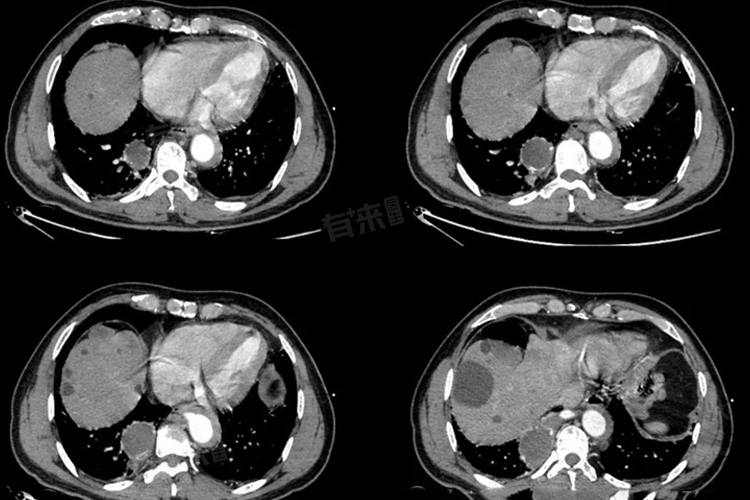

肺叶切除属于大手术。肺叶切除是指通过外科手术的方式,将病变的肺叶从人体肺部完整切除,以达到治疗疾病的目的,常见于肺癌、严重的肺部感染、肺囊肿等疾病的治疗。

- 胸腔镜手术虽相对微创,但也需要在胸腔内进行精细操作,在胸壁上打几个小孔,通过特殊器械切除肺叶。肺叶周围有丰富的血管、支气管等重要结构,手术中需要仔细分离、结扎和切断肺动静脉以及支气管,操作过程精细且复杂,稍有不慎就可能损伤周围血管导致大出血,或损伤支气管残端,影响术后愈合。

- 肺叶切除后,肺的有效气体交换面积减少,必然会对呼吸功能产生显著影响。患者术后可能会出现不同程度的呼吸困难、气短等症状,尤其是在运动或体力活动时更为明显。而且,肺部与心脏紧密相连,肺循环发生改变,可能导致心脏负担加重,长期来看,可能会对心脏功能产生一定影响,如出现心律失常等情况。